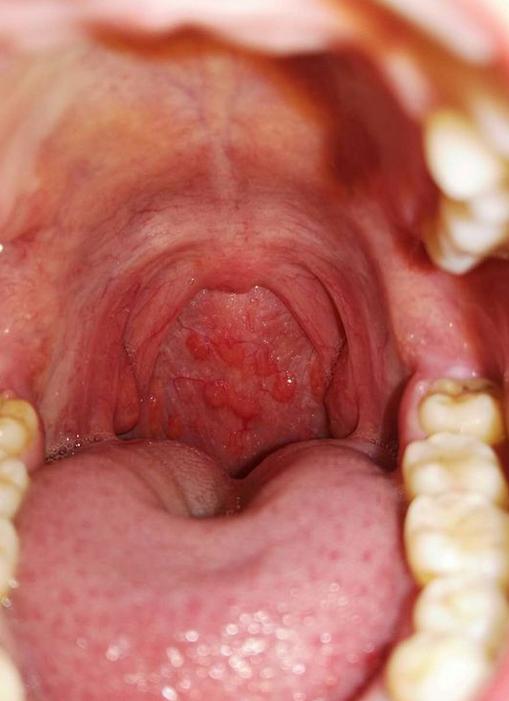

⑤ 喉咙舌根底部、舌头顶部有小泡泡,小疙瘩情况,尤其有烟酒习惯男士,爱辛辣刺激食物,长期过渡用嗓人群等,出现这种症状是淋巴滤泡性咽炎。